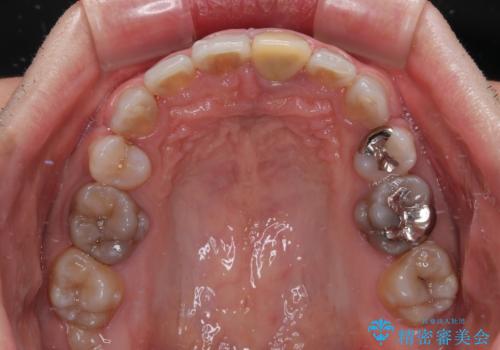

- 口元の突出感を改善するための抜歯矯正を終えた患者様ですが、幼少期からの変色した歯をセラミッククラウンにて自然な色合いに変えていくこととしました。

口を開けたときに目につく範囲を希望されたため上下ともに8本ずつをオールセラミッククラウンによる補綴治療を行うこととしました。

近年では大変珍しいですが、胎児あるいは乳幼児期の抗生物質の影響で永久歯が変色してしまうことがあります。

ホワイトニングでの改善は期待できないため、オールセラミッククラウンによる補綴治療が必要となります。